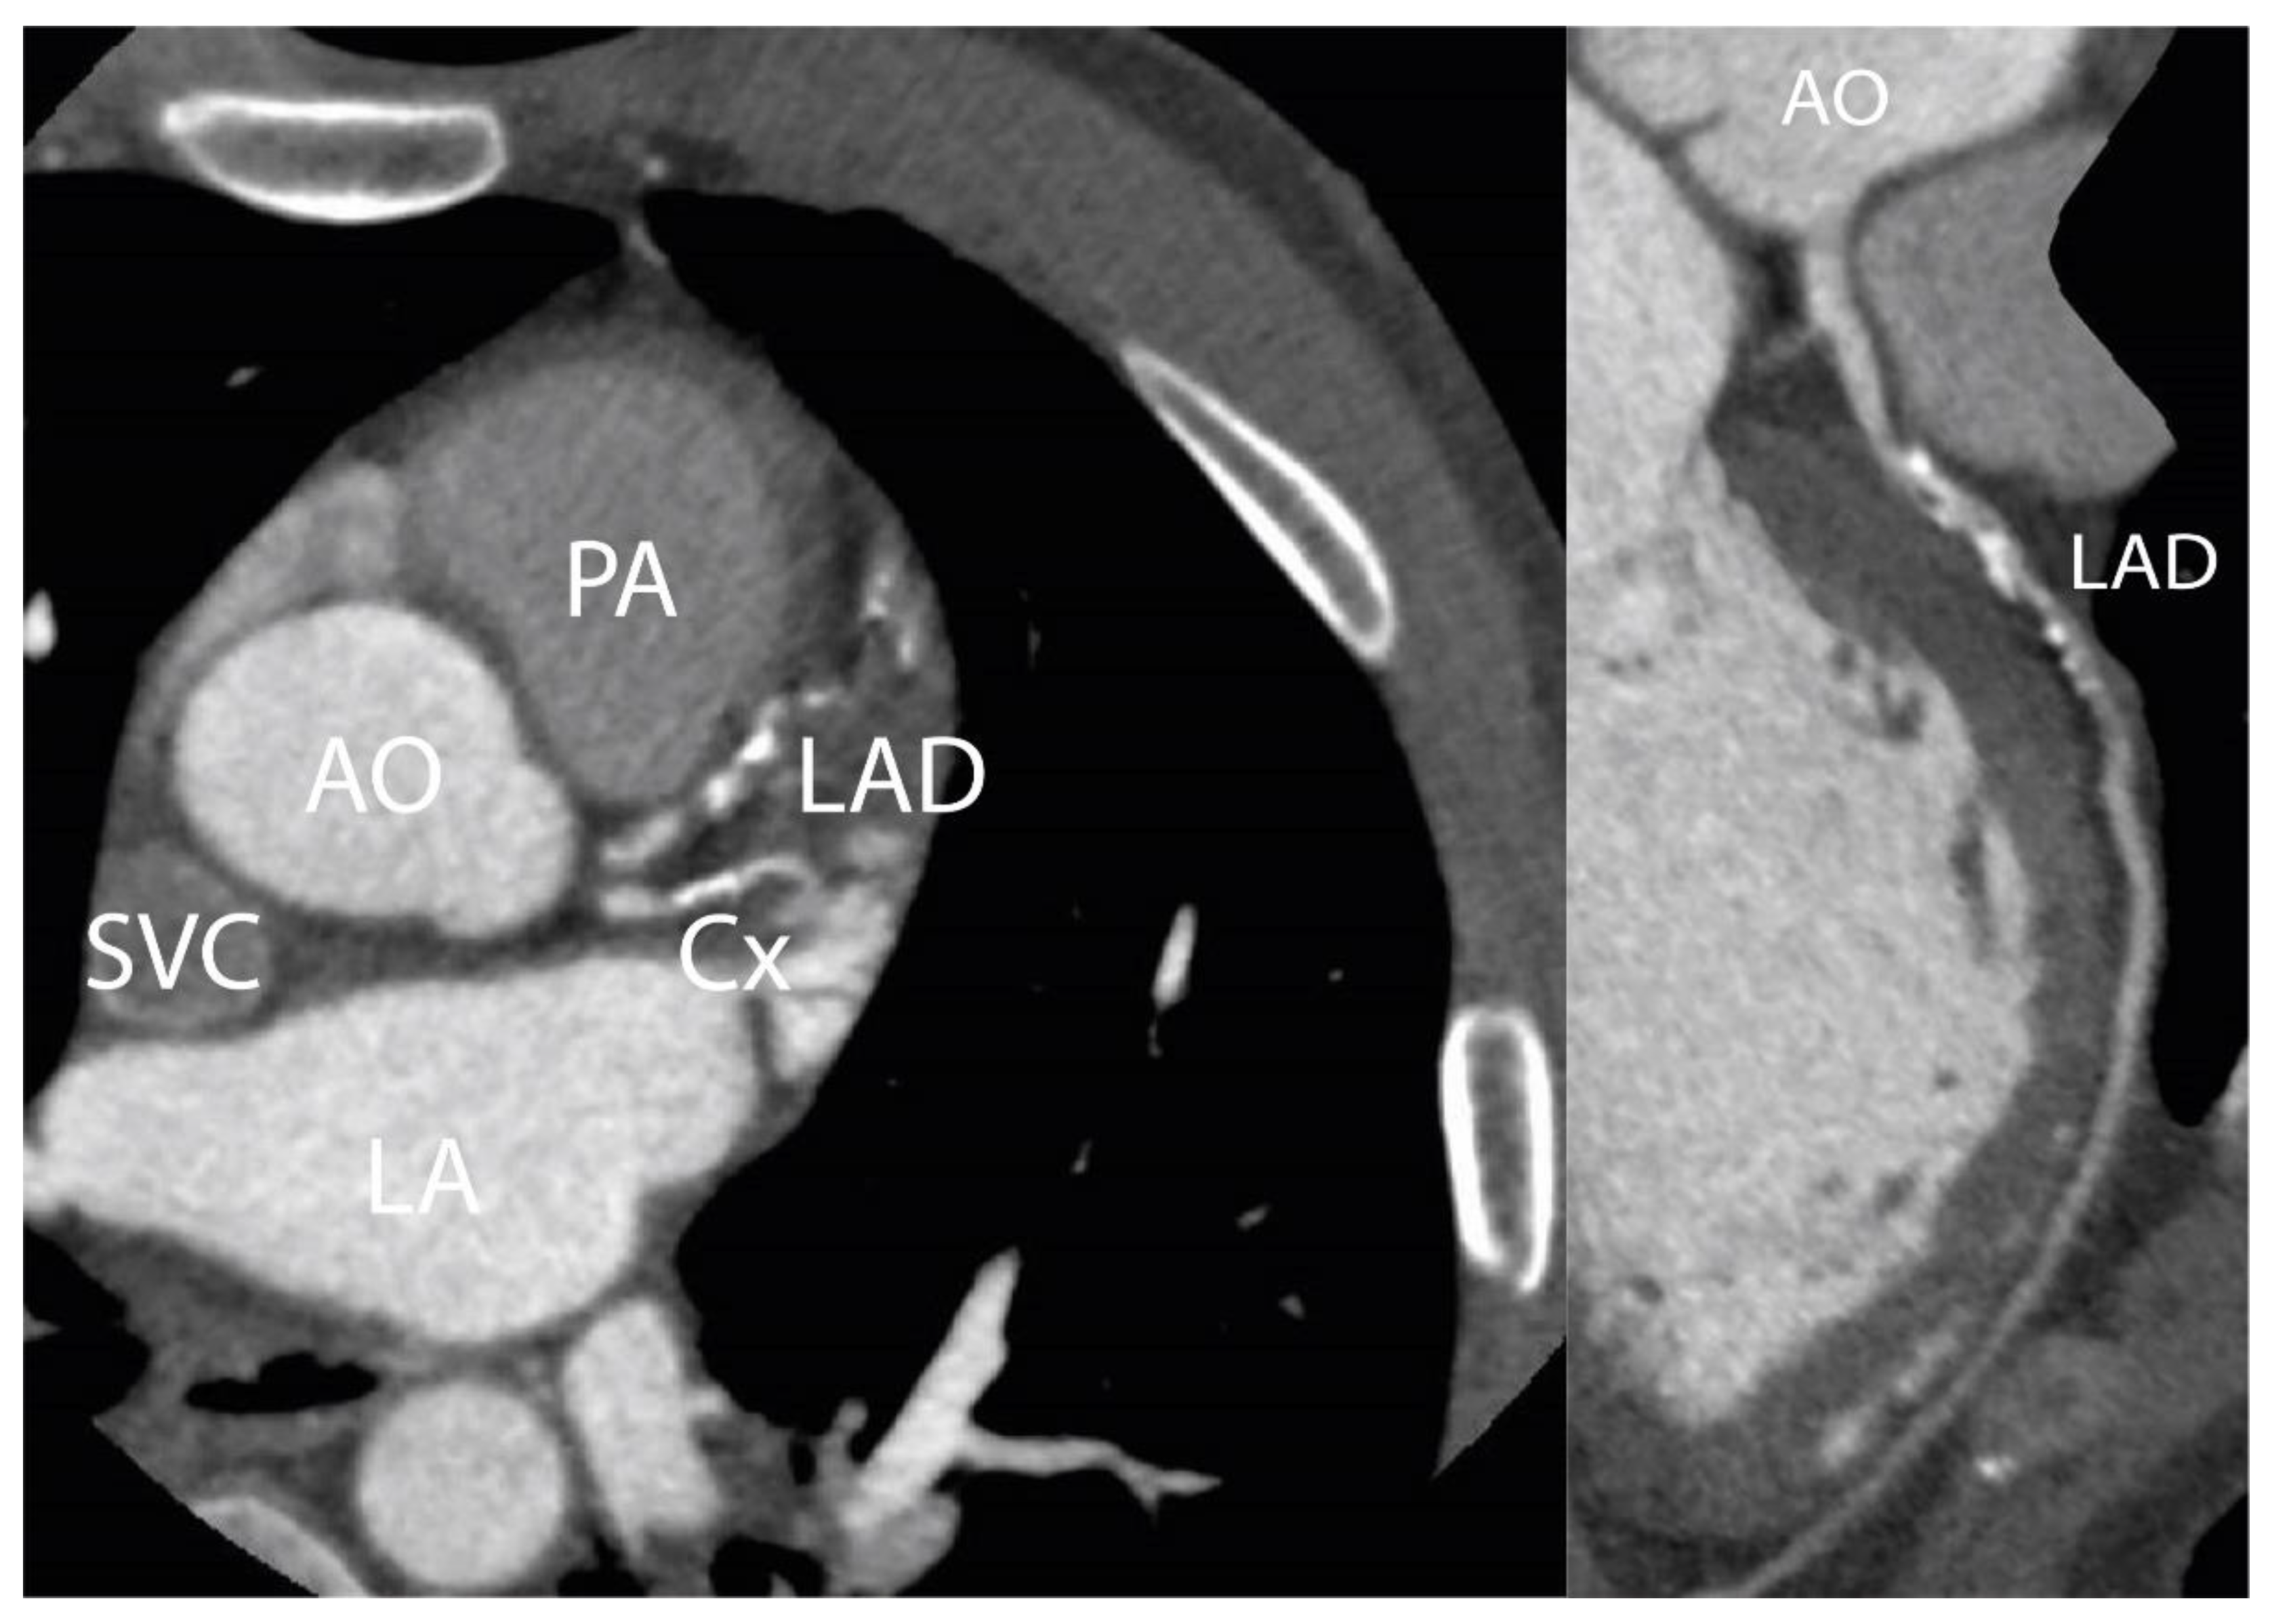

Appendix A.1. Patient A. Male, 46 Years

Appendix A.2. Patient B. Male, 45 Years